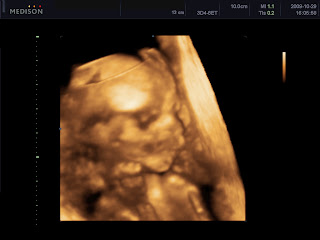

Drukkoljatok lányok, ma megyek genetikai UH-ra 12:00-re, már nagyon izgulok!

Remélem sikerül csináltatnom róla egy 4 D-s fotót! Ja és végre biztos lesz a neme is! :)

No, most értünk haza a potya UH-ról, beengedték a férjeket is, sőt, egy szobában volt több gép, sőt, CD-t is írtak....éééés FIÚÚÚÚ! Ez már biztos :) hamarosan mondom a nevét is, de több, mint valószínű, hogy Ábel lesz.....

Íme egy fotó, Kedves beleművészkedett, hogy egyértelműbb legyen. Engem egy kedves indiai nőce vizsgált, ő volt a tanító, és ketten vizsgálódtak még. Sokáig nézte a szívét, azt mondta, hogy olyan szülészorvost keressek, aki tudja követni a baba szívét, mert valami olyat észlelt, hogy aszinkronocitás van, nem nagy baj, csak valami nem pont egyszerre működik.....nem egyszerre húzódik össze, vagy valami ilyesmi... Kép